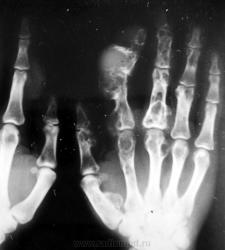

Пол пациента: Мужской пол Тип патологии: Врожденная патология Область исследования: Скелетно-мышечная система Методы исследования: Rg Думаю, что особых трудностей наблюдение вызвать не должно. Хотя... https://radiomed.ru/sites/default/files/styles/case_slider_image/public/user/1954/PICT3973.JPG?itok=5slXKF68 ID:343 Цель публикации: Консультация Вс, 17/01/2010 - 14:17 #1 Катенёв Валенти... Не на сайте Был на сайте: 7 лет 2 недели назад Зарегистрирован: 22.03.2008 - 22:15 Публикации: 54876 На мой взгляд, "картинка" даже более информативная, чем у Рейнберга. Вс, 17/01/2010 - 14:20 #2 Петрович Не на сайте Был на сайте: 7 лет 2 месяцев назад Зарегистрирован: 22.03.2009 - 01:13 Публикации: 3908 На первый взгляд множественные энхондромы. Неоднозначно всё Вс, 17/01/2010 - 14:31 #3 Анатолий Владим... Не на сайте Был на сайте: 7 лет 10 месяцев назад Зарегистрирован: 16.10.2009 - 21:16 Публикации: 1941 Тут оба вида роста во всей красе...

На мой взгляд, "картинка" даже более информативная, чем у Рейнберга.

На первый взгляд множественные энхондромы.

Неоднозначно всё

Тут оба вида роста во всей красе...